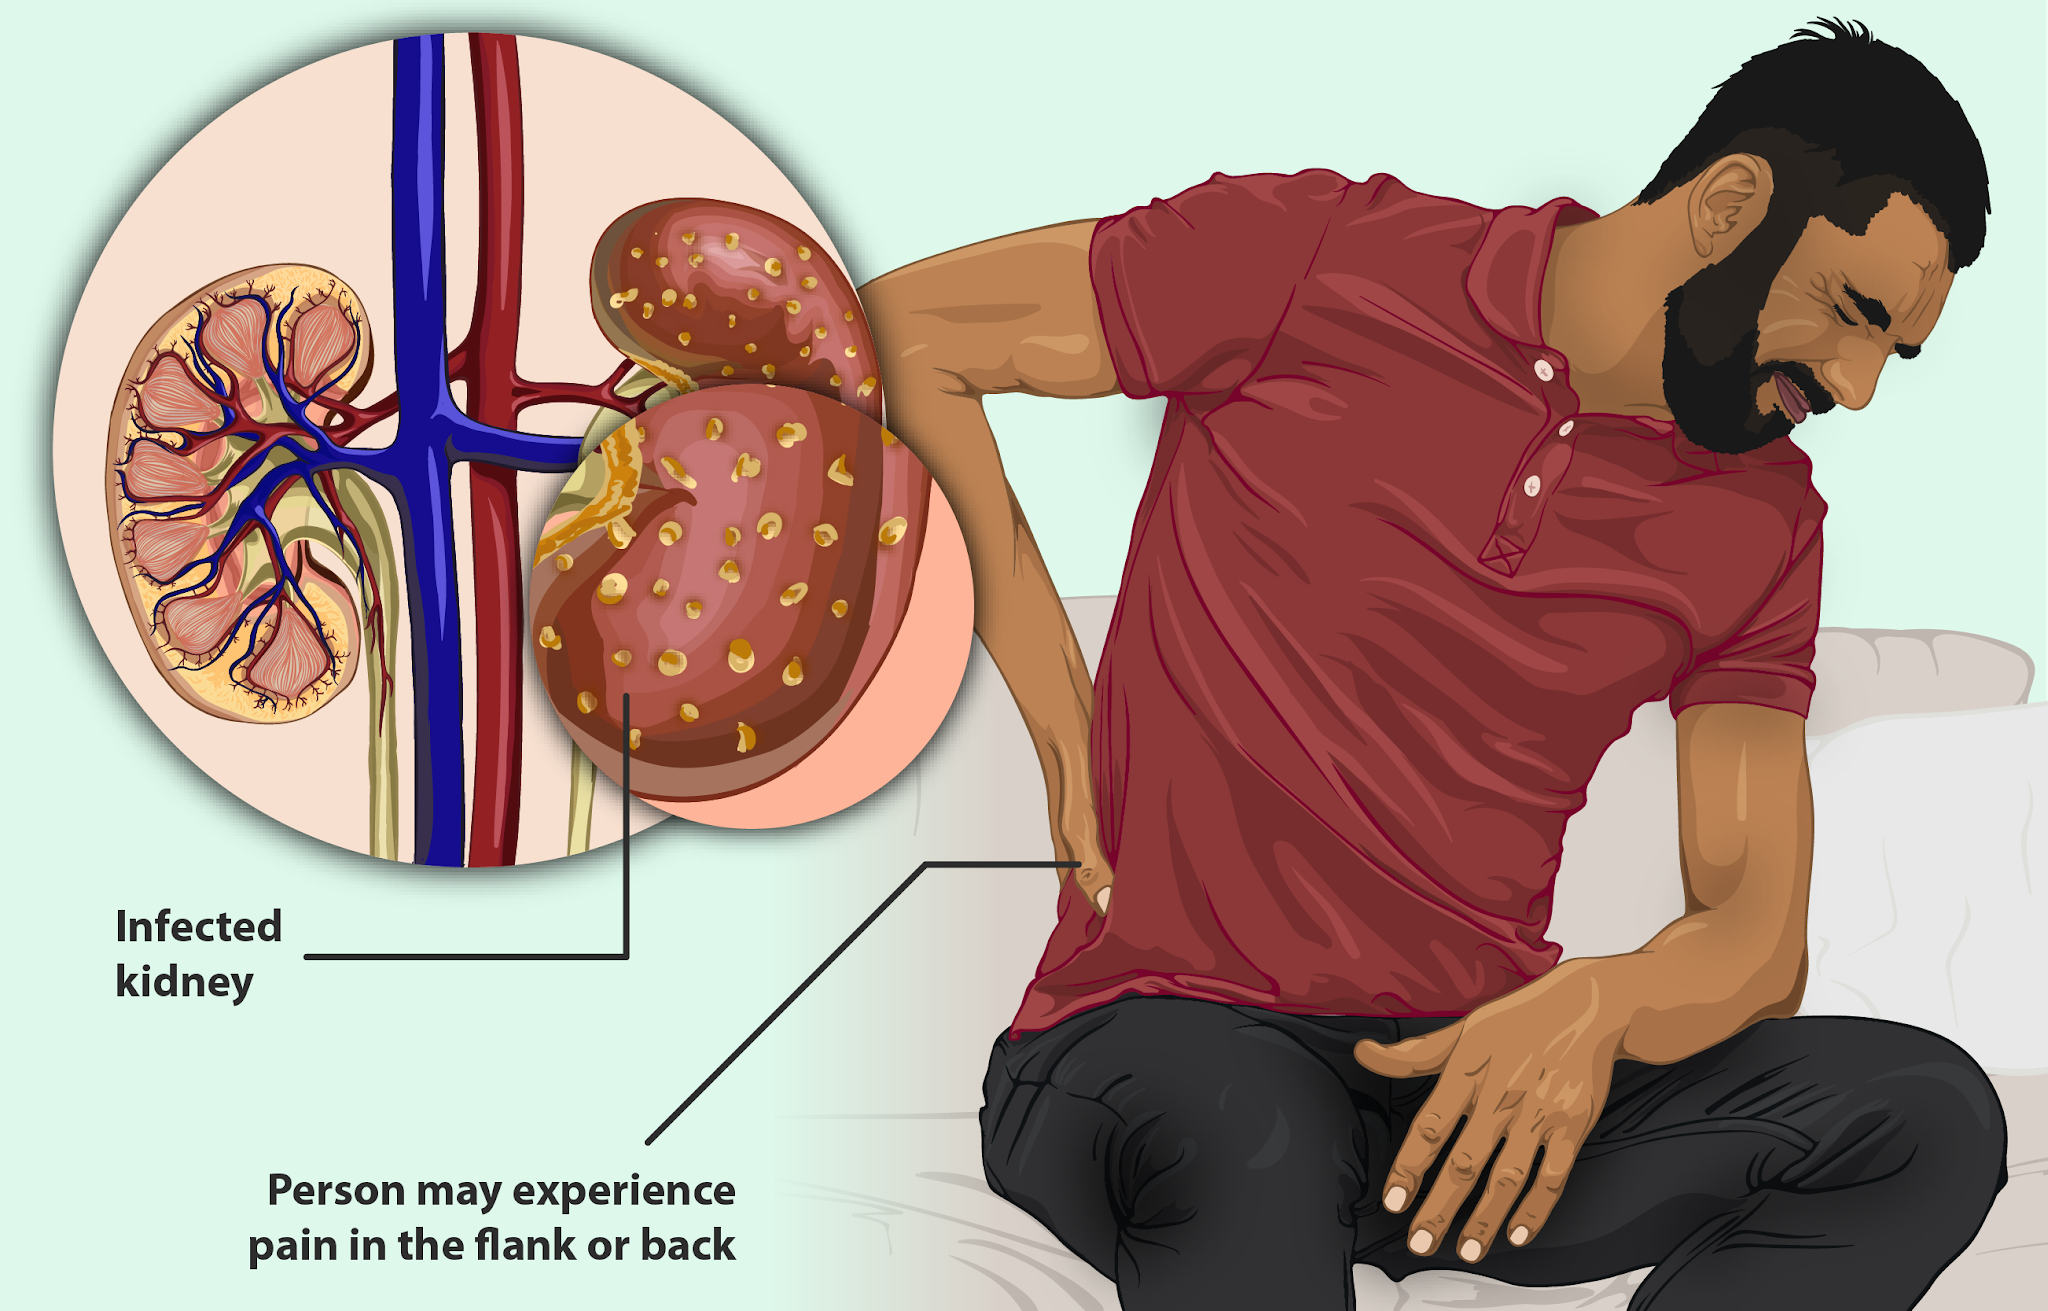

الوصفات التقليدية والخلطات الطبيعية تساعد في الحد من الأمراض المرتبطة بالتقدم بالعمر مثل خمول العضلات وارتفاع مستوى الكوليسترول في الدم، وتمرير الرواسب والأملاح في الكلى قد يسبب العديد من الأعراض مثل آلام الكلى على أحد جانبيها أو كلاهما. يمكن أن تكون الأسباب حصوات الكلى أو الكيس المائي على الكلى، ويمكن استخدام الأعشاب الطبيعية للتخفيف من هذه الأعراض الجانبية.

تظهر علامات تكيس الكلى الأولية عادة على شكل آلام متنوعة، ويمكن أن تشمل:

- ألام أسفل الظهر.

- ألام أحد جانبي البطن أو كلاهما.